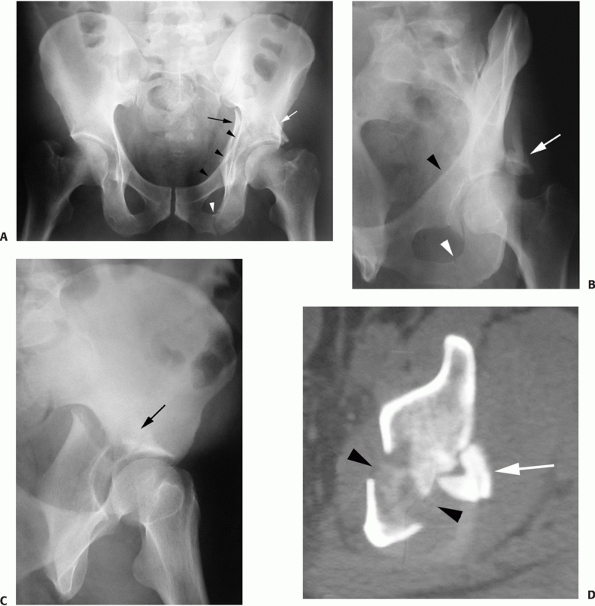

FIGURE 45-17 Radiographic appearance of the posterior column fracture. A. On the anteroposterior view, the displacement of the ilioischial line (arrow) is apparent while the iliopectineal line is seen to be intact (black arrowheads). As typical, the ilioischial line (arrow) is displaced relative to the radiographic U (white arrowhead). B. The obturator oblique view confirms the anterior column to be intact (arrowheads) and demonstrates the fracture of the ischial ramus (arrow). C. The iliac oblique view shows the disruption of the greater sciatic notch and the displacement of the posterior column (arrow). D. The computed tomography section shows a fracture line typical of a posterior column fracture. (Copyright Berton R. Moed, MD.)

the entire ischioacetabular segment from the innominate bone and

represent 3% to 5% of acetabular fractures.78,83,90

The fracture begins at the posterior border of the innominate bone,

near the apex of the greater sciatic notch. It descends across the

articular surface, quadrilateral surface, ischiopubic notch (roof of

the obturator canal), and finally across the inferior ramus. On the AP

radiograph, the ilioischial line, the posterior rim, and the inferior

ramus are disrupted. The disruption of the posterior rim will be seen

in only one location, where the fracture line crosses the rim. This is

in distinction to the posterior wall fracture where the posterior rim

will be seen to be disrupted in two locations, separating a portion of

the articular surface. The iliac oblique radiograph demonstrates the

fracture crossing the posterior border of the bone. The fracture of the

ischiopubic ramus and posterior rim are confirmed on the obturator

oblique. The iliopectineal line is preserved on all views. The femoral

head follows the displacement of the posterior column posteriorly and

medially (Fig. 45-17). The ilioischial line is typically displaced relative to the radiographic U (Fig. 45-17A).

However, when a large portion of the quadrilateral surface remains